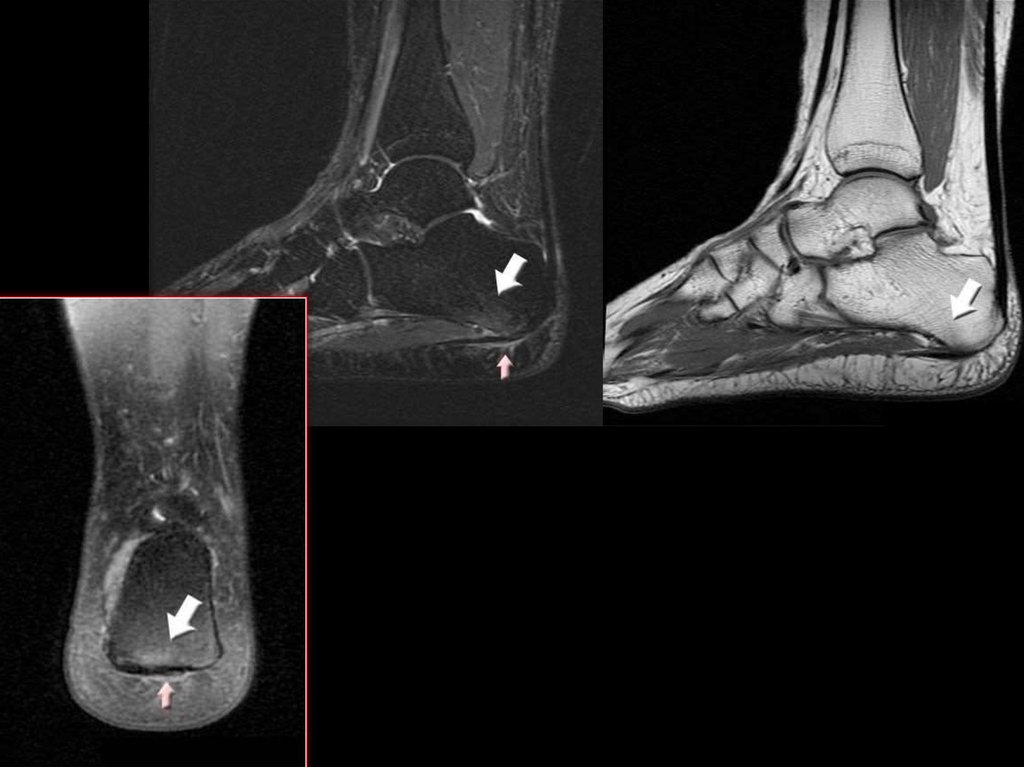

47. Плантарный фасциит («пяточная шпора»)

49.

50.

51. Тендинит ахиллового сухожилия

53. Подкожный бурсит ахиллового сухожилия